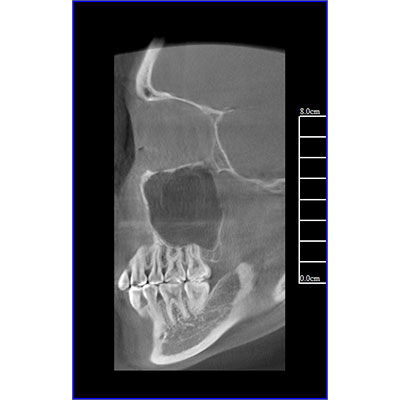

專有三維重建算法,可提供任意位置高清斷層影像。

可同時(shí)觀察軸向面、冠狀面和矢狀面圖像,方便臨床診斷。